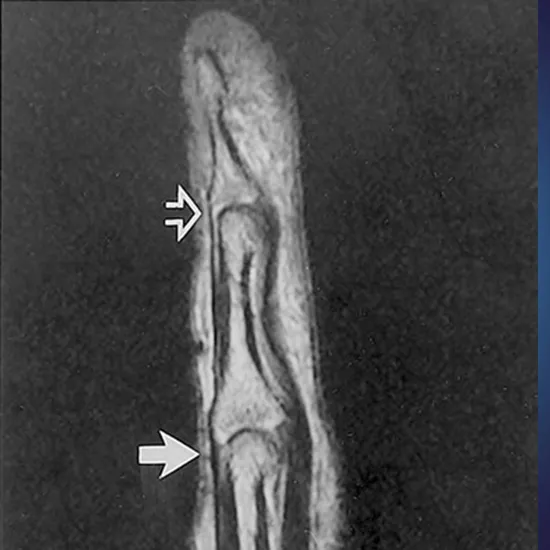

MRI index finger is an imaging technique is used for index finger anatomy. It obtains a high resolution picture to view the bones, the surrounding soft tissues like the cartilage, tendons, ligaments, muscles, and blood vessels, etc.

Doctors recommend an MRI index finger to diagnose bones fracture, signs of suspected arthritis, soft tissue injuries, joint dislocation, ligament or tendon injury, suspected infection, osteoporosis, bone deformities, tumors, abnormal bone growth, blockage of blood vessels, etc.